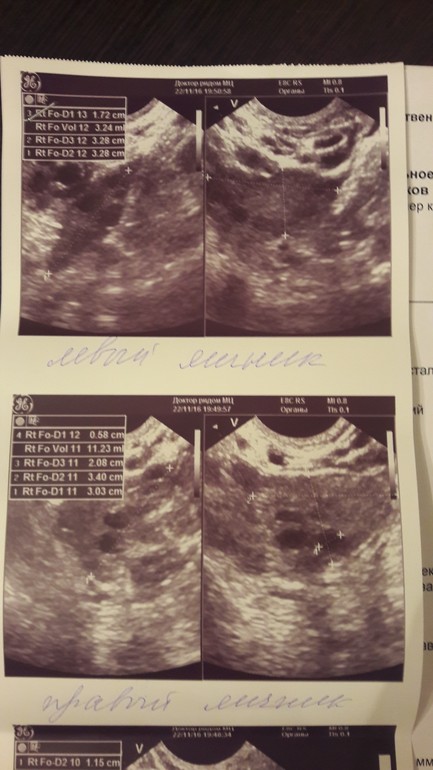

Посмотрите УЗИ

Была сегодня на УЗИ, 12 ДЦ, думала перед О сходить, а получилось что она уже была. Это конечно хорошая новость, что О вообще есть, а вот остальное не порадовало.

В общем ниже УЗИ, гормоны на 5 ДЦ и график БТ. Что скажете?

Вопрос когда была О можно понять? Хотела прогик сдать, а теперь даже не знаю на какой ДЦ сдавать.

Похоже на 7 дц, но почему вчера так упала бт... Можно было б еще предполржить, что вчера, но по гормонам видно, что уже вторая фаза. А узи и гормоны когда сдавали? И как на 7дц як могла перезреть?) Падение вчера вдруг ИЗ?